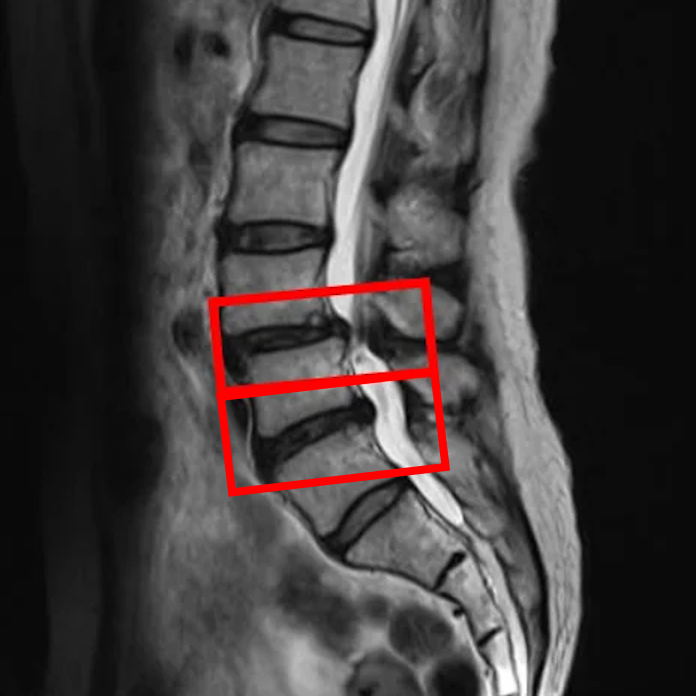

По данным МРТ и результатам осмотра пациентки выявлены межпозвоночные грыжи дисков L4/L5, L5/S1, а также стеноз позвоночного канала.

В клинике проведена селлгель-терапия на 2 межпозвоночных дисках.